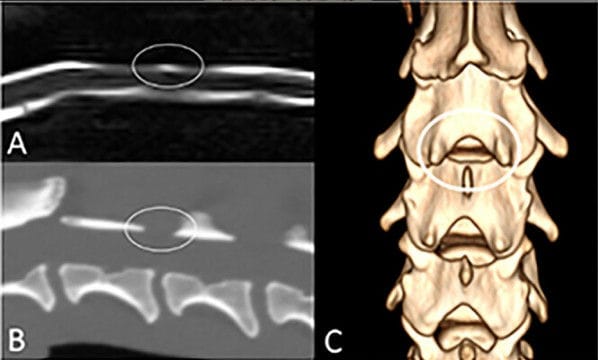

Cervical MRI study of an 11-year-old Dachshund with an acute HNPE at C3-4. (A) Sagittal MR myelogram shows a lack of attenuation of the dorsal subarachnoid space at C3-4 (oval). (B) Sagittal reconstructed CT image of the neck of the same dog showing the interarcuate space at C3-4, corresponding to the location of maintained signal in the subarachnoid space (oval). (C) Dorsal view of a 3D volume rendered image of the cervical spine provides a clear view of the interarcuate space at C3-4 (oval). Note also the large interarcuate spaces at C4-5 and C5-6.

Thirty-four dogs were included, with one dog contributing two cases, resulting in 35 MRI studies. The most common sites of HNPE were C4–5 and C3–4. The dorsal subarachnoid space remained visible on MR myelograms in 25 of 35 cases (71.4%), while attenuation occurred in 10 cases (28.6%). The degree of spinal cord compression was similar regardless of whether the dorsal subarachnoid space remained visible. In cases with available CT imaging, the retained CSF signal corresponded anatomically to the interarcuate space—the gap between adjacent vertebral arches—suggesting this structure allows focal dorsal expansion of the subarachnoid space.

Failure of the dorsal subarachnoid space to attenuate on MR myelography is common in dogs with cervical HNPE and does not correlate with the severity of spinal cord compression. This phenomenon is likely explained by displacement of the dorsal subarachnoid space into the interarcuate space between adjacent vertebral arches. Recognizing this imaging pitfall is important, as reliance on circumferential CSF attenuation alone may lead to underestimation or missed diagnosis of compressive cervical myelopathy. Careful evaluation of other MRI indicators of spinal cord compression remains essential.